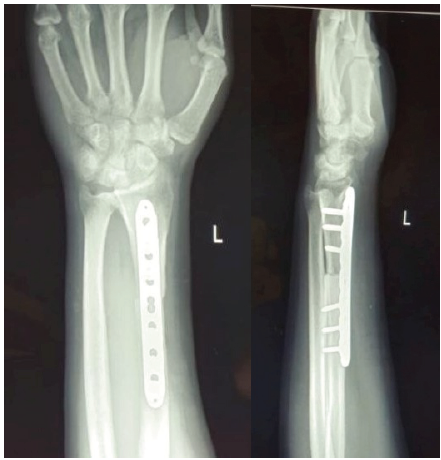

A representative example of Case 1 is illustrated in Figures 1–6. The preoperative radiograph is shown in Figure 1, while Figure 2 demonstrates the MRI findings confirming avascular necrosis of the lunate. Figures 3–5 depict the immediate postoperative radiographs and sequential follow-up images up to 1 year. Figure 6 shows the final clinical photograph, demonstrating a good functional outcome.

Figure 4: At 6 months follow-up, anteroposterior and lateral radiographs demonstrated stable fixation with maintained reduction, effective lunate unloading, and satisfactory evidence of healing with bony union. Clinically, the patient reported significant pain relief and improvement in wrist function.